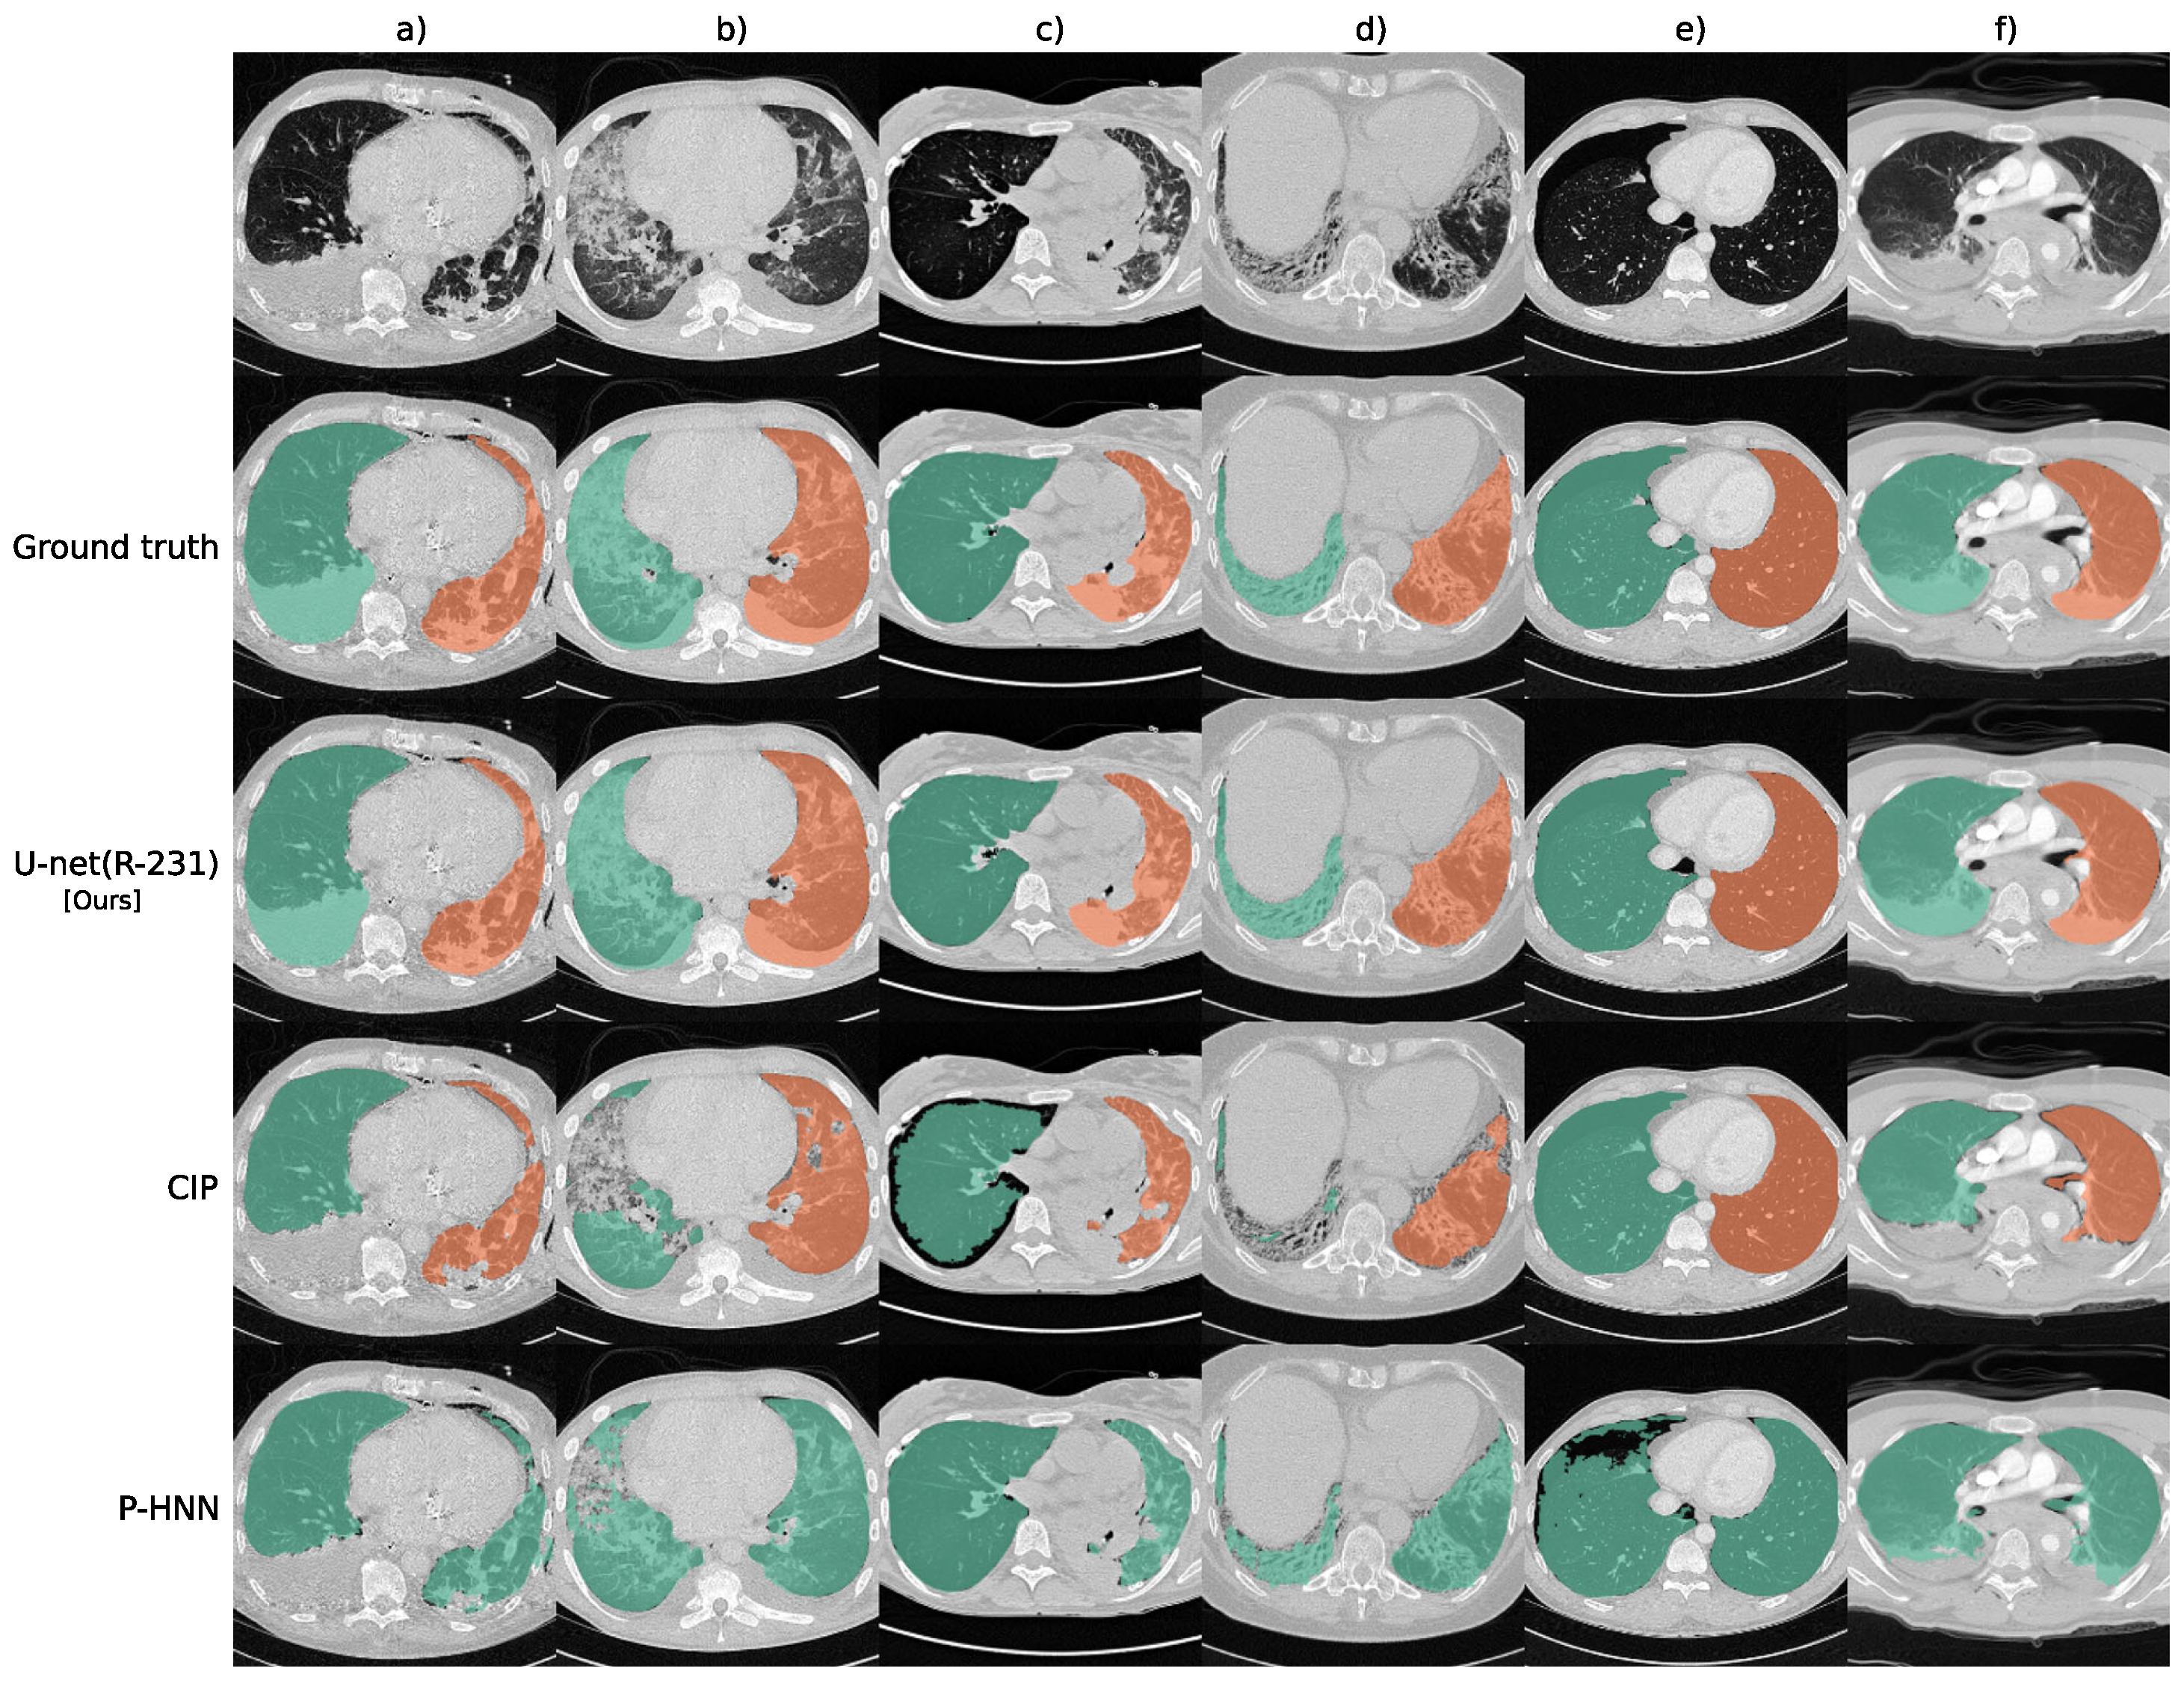

5. Lung Segmentation

- Hofmanninger, J.; Prayer, F.; Pan, J.; Röhrich, S.; Prosch, H.; Langs, G. Automatic lung segmentation in routine imaging is primarily a data diversity problem, not a methodology problem. Eur. Radiol. Exp. 2020, 4, 1–13. [Google Scholar] [CrossRef] [PubMed]